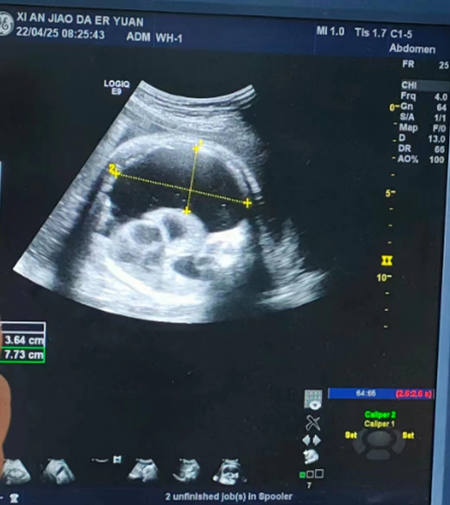

2022年4月25日早晨,二附院妇儿医学MDT团队迅速启动危重孕产妇及胎儿救治团队,对孕妈妈患者实行紧急剖宫产手术,胎儿出生后立即进行气管插管辅助通气,同时实施超声引导下胸腔闭式引流,严重胸腔积液胎儿重获新生。

26岁的孕妈妈付女士,在孕37周时因“羊水过多”来到西安交大二附院产科段钊副主任门诊。经段钊认真询问病史发现,付女士几年前因“胎儿畸形”无奈引产,失去做母亲的梦想,试管婴儿多次才即将迎来珍贵“虎宝宝”。孕前检查夫妇双方染色体核型正常,孕期产检B超提示持续性右脐静脉,其余常规产检、检验检查均未见异常,未行羊水穿刺产前诊断。不料距离预产期仅一月的时间,忽然发现腹部膨隆明显,羊水增多,进一步检查发现胎儿右侧胸腔大量积液,右肺明显受压,体积变小,心脏及左肺受压向左移位,食管受压影响胎儿吞咽功能,羊水量明显增多,这让付女士一家人又焦虑起来。经当地医院转诊,付女士来到了西安交大二附院,接受住院治疗。

面对这样“特殊”的孕妇,产科医护人员高度重视,迅速启动危重孕产妇及胎儿救治团队多学科会诊,团队涵盖新生儿内科、新生儿外科、手术科室、麻醉科室、呼吸内科、心血管内科、重症医学科等10余名经验丰富的专家,各位专家对该患儿深入讨论后,总结了胎儿可能面临的各种危险,胸腔积液严重、纵膈右移、气道右移、心脏右移,孕期不采取干预措施,怀孕后期胎儿水肿风险增加,胎儿死亡机率增大。各位主任们集思广益,从病例的发病机制、临床表现、影像学特点出发,再到患者的功能预后,最终决定对患者实行紧急剖宫产手术,胎儿出生后立即进行气管插管辅助通气,同时实施超声引导下胸腔闭式引流。所有医护人员准备就绪,“可以开始!”,段钊稳稳地拿着手术刀划开付女士皮肤,产科团队默契配合,一层层薄薄的腹部组织和子宫被精准切开,凭借精湛的医疗技术,手术一气呵成。新生儿科医师及助产士组成的新生儿复苏小组在手术室严阵以待,他们立即接过婴儿,给予新生儿复苏、吸氧、保暖、体外胸腔引流置管术等专业检查和处置,顺利引出胸腔积液500ml。新生儿复苏成功后,产科助产士和儿科医生共同将其护送到新生儿监护室。